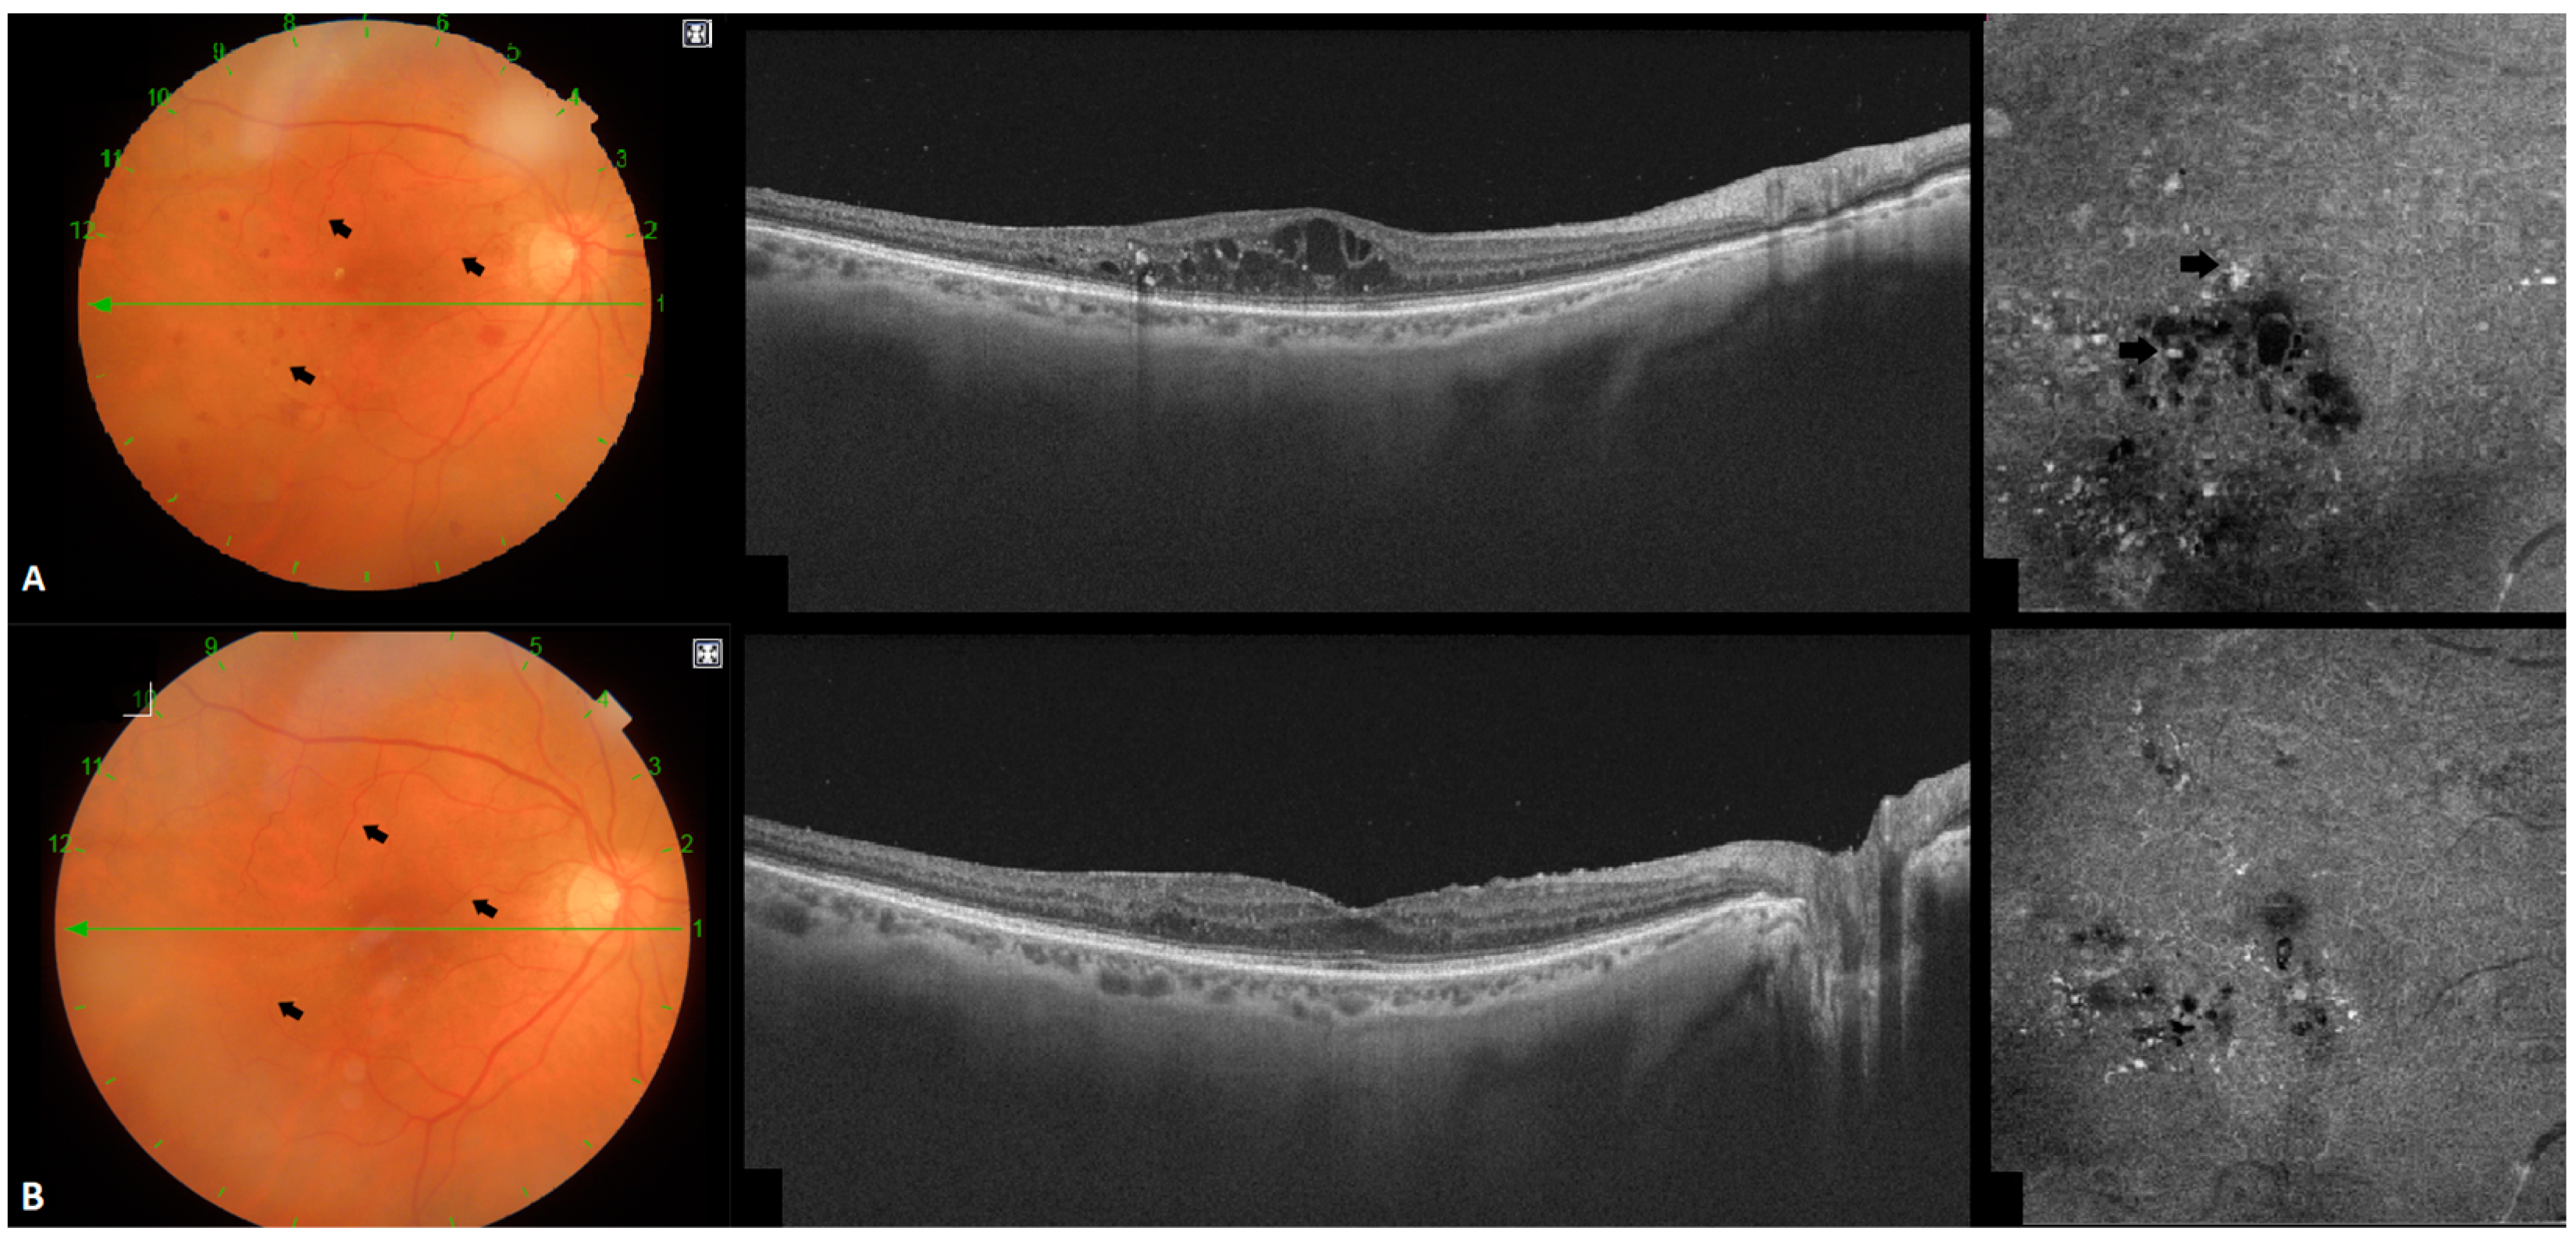

3.1. Location of MAs and Their Influence in DME